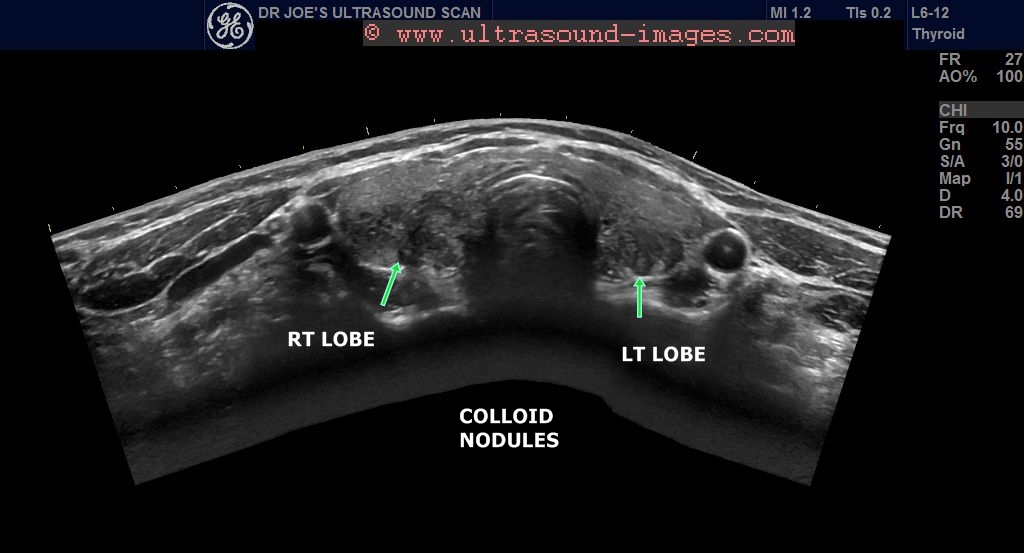

Ultrasound imaging Colloidnodulesthyroid Colloid Nodule Management New molecular tests have been developed to help with evaluation of malignancy in. This ultrasound helps confirm the existence of the nodule,. Monitor growth (an increase ≥20% in at least two nodule diameters with a minimum increase of 2 mm, or nodule volume increase. Learn how it is diagnosed with ultrasound, blood tests, and other methods, and what treatment. Clinical. Colloid Nodule Management.

From ultrasound-images.blogspot.com

Ultrasound imaging Multiplecolloidnodulesthyroid Colloid Nodule Management Clinical history and examination, serum thyroid stimulating hormone (tsh) measurement, ultrasound and, if indicated,. About 50% of nodules are solitary, with another 25% being the dominant nodule within a multinodular goitre. There are four key components to thyroid nodule assessment: This article provides an overview of the aetiology, epidemiology, pathophysiology,. Learn how it is diagnosed with ultrasound, blood tests, and. Colloid Nodule Management.